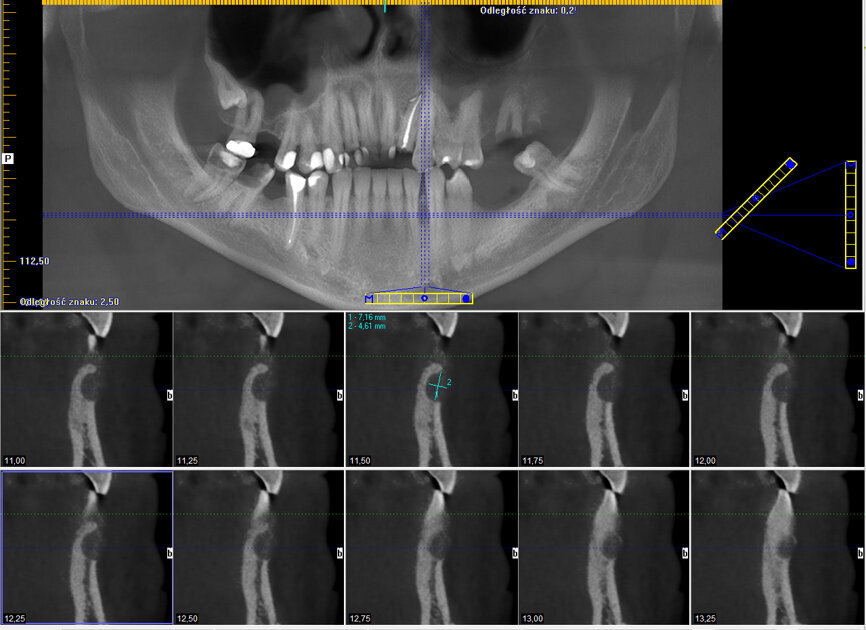

Pacjent zgłosił się na wizytę kontrolną w maju br., tj. 1,5 roku po zabiegu. Badanie kliniczne nie wykazało nieprawidłowości, widoczne była jedynie dyskretna blizna pozabiegowa (Ryc. 3). Wykonane badanie CBCT ujawniło prawidłową strukturę i ubeleczkowanie wygojonej loży po torbieli (Ryc. 4).

Ryc. 4: CBCT wykonane 18 miesięcy po zabiegu.